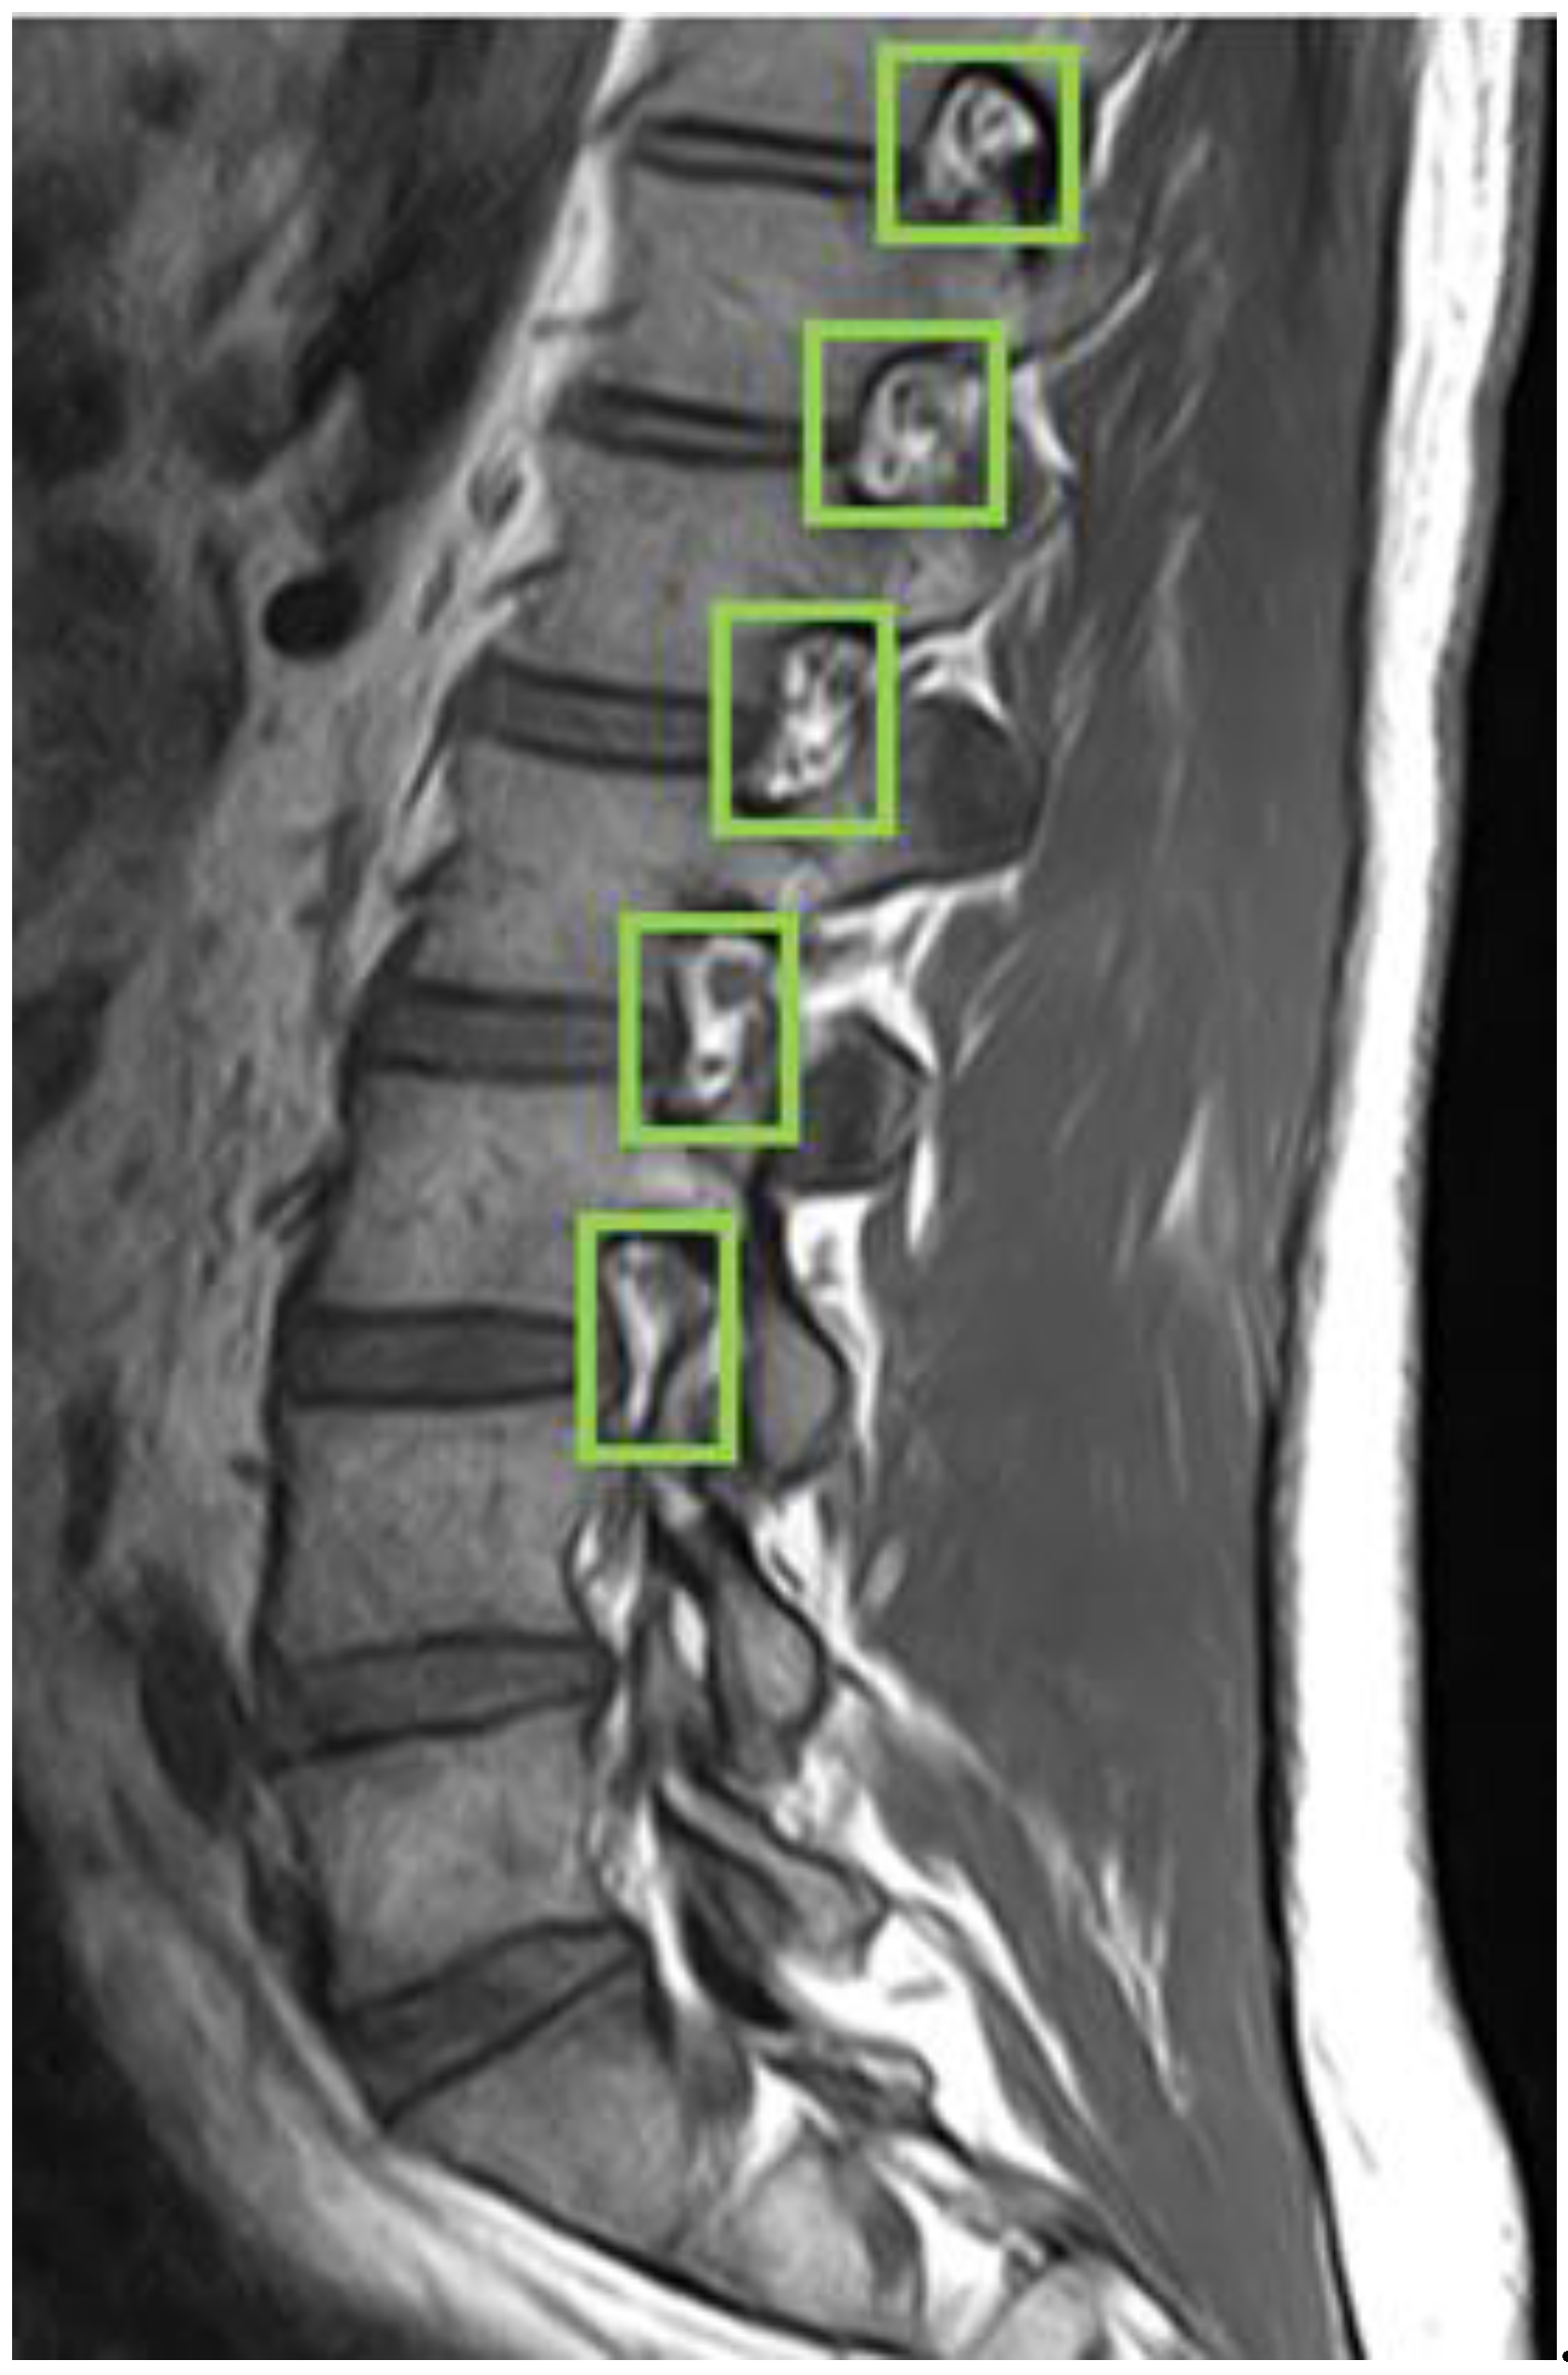

First, we used LabelImg software to delineate the rectangular region of the intervertebral foramen. The annotations were made in YOLO format, with the intervertebral foramen as the sole labeled class. Figure 5 shows an example of a light green-colored annotated intervertebral foramen MRI image.

Figure 5. Use LabelImg tool to annotate intervertebral foramen MRI image.